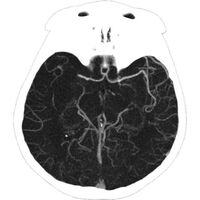

Врачи спасли россиянку от инсульта, удалив из мозга гигантский 25-сантиметровый тромб

Московские хирурги спасли молодую женщину от инсульта, удалив огромный тромб из мозговой артерии. Об этом сообщает столичный Депздрав.

25-летняя женщина поступила в ГКБ им. М.П. Кончаловского с жалобами на головокружение, слабость и онемение конечностей. Медики диагностировали у нее ишемический инсульт.

«Из артерии удалось извлечь червеобразный сгусток длиной 25 см. Изначально мы даже заподозрили, что в сосуде мозга женщины поселился паразит. Но исследования показали, что это все-таки тромб», — рассказал руководитель регионального сосудистого центра Владимир Кузнецов.

После операции пациентка прошла углубленное обследование, которое показало, что у нее развилось опасное аутоиммунное заболевание — антифосфолипидный синдром, при котором возрастает риск образования тромбов в артериях и венах. Женщине подобрали лечение, которое в дальнейшем будет препятствовать образованию тромбов.